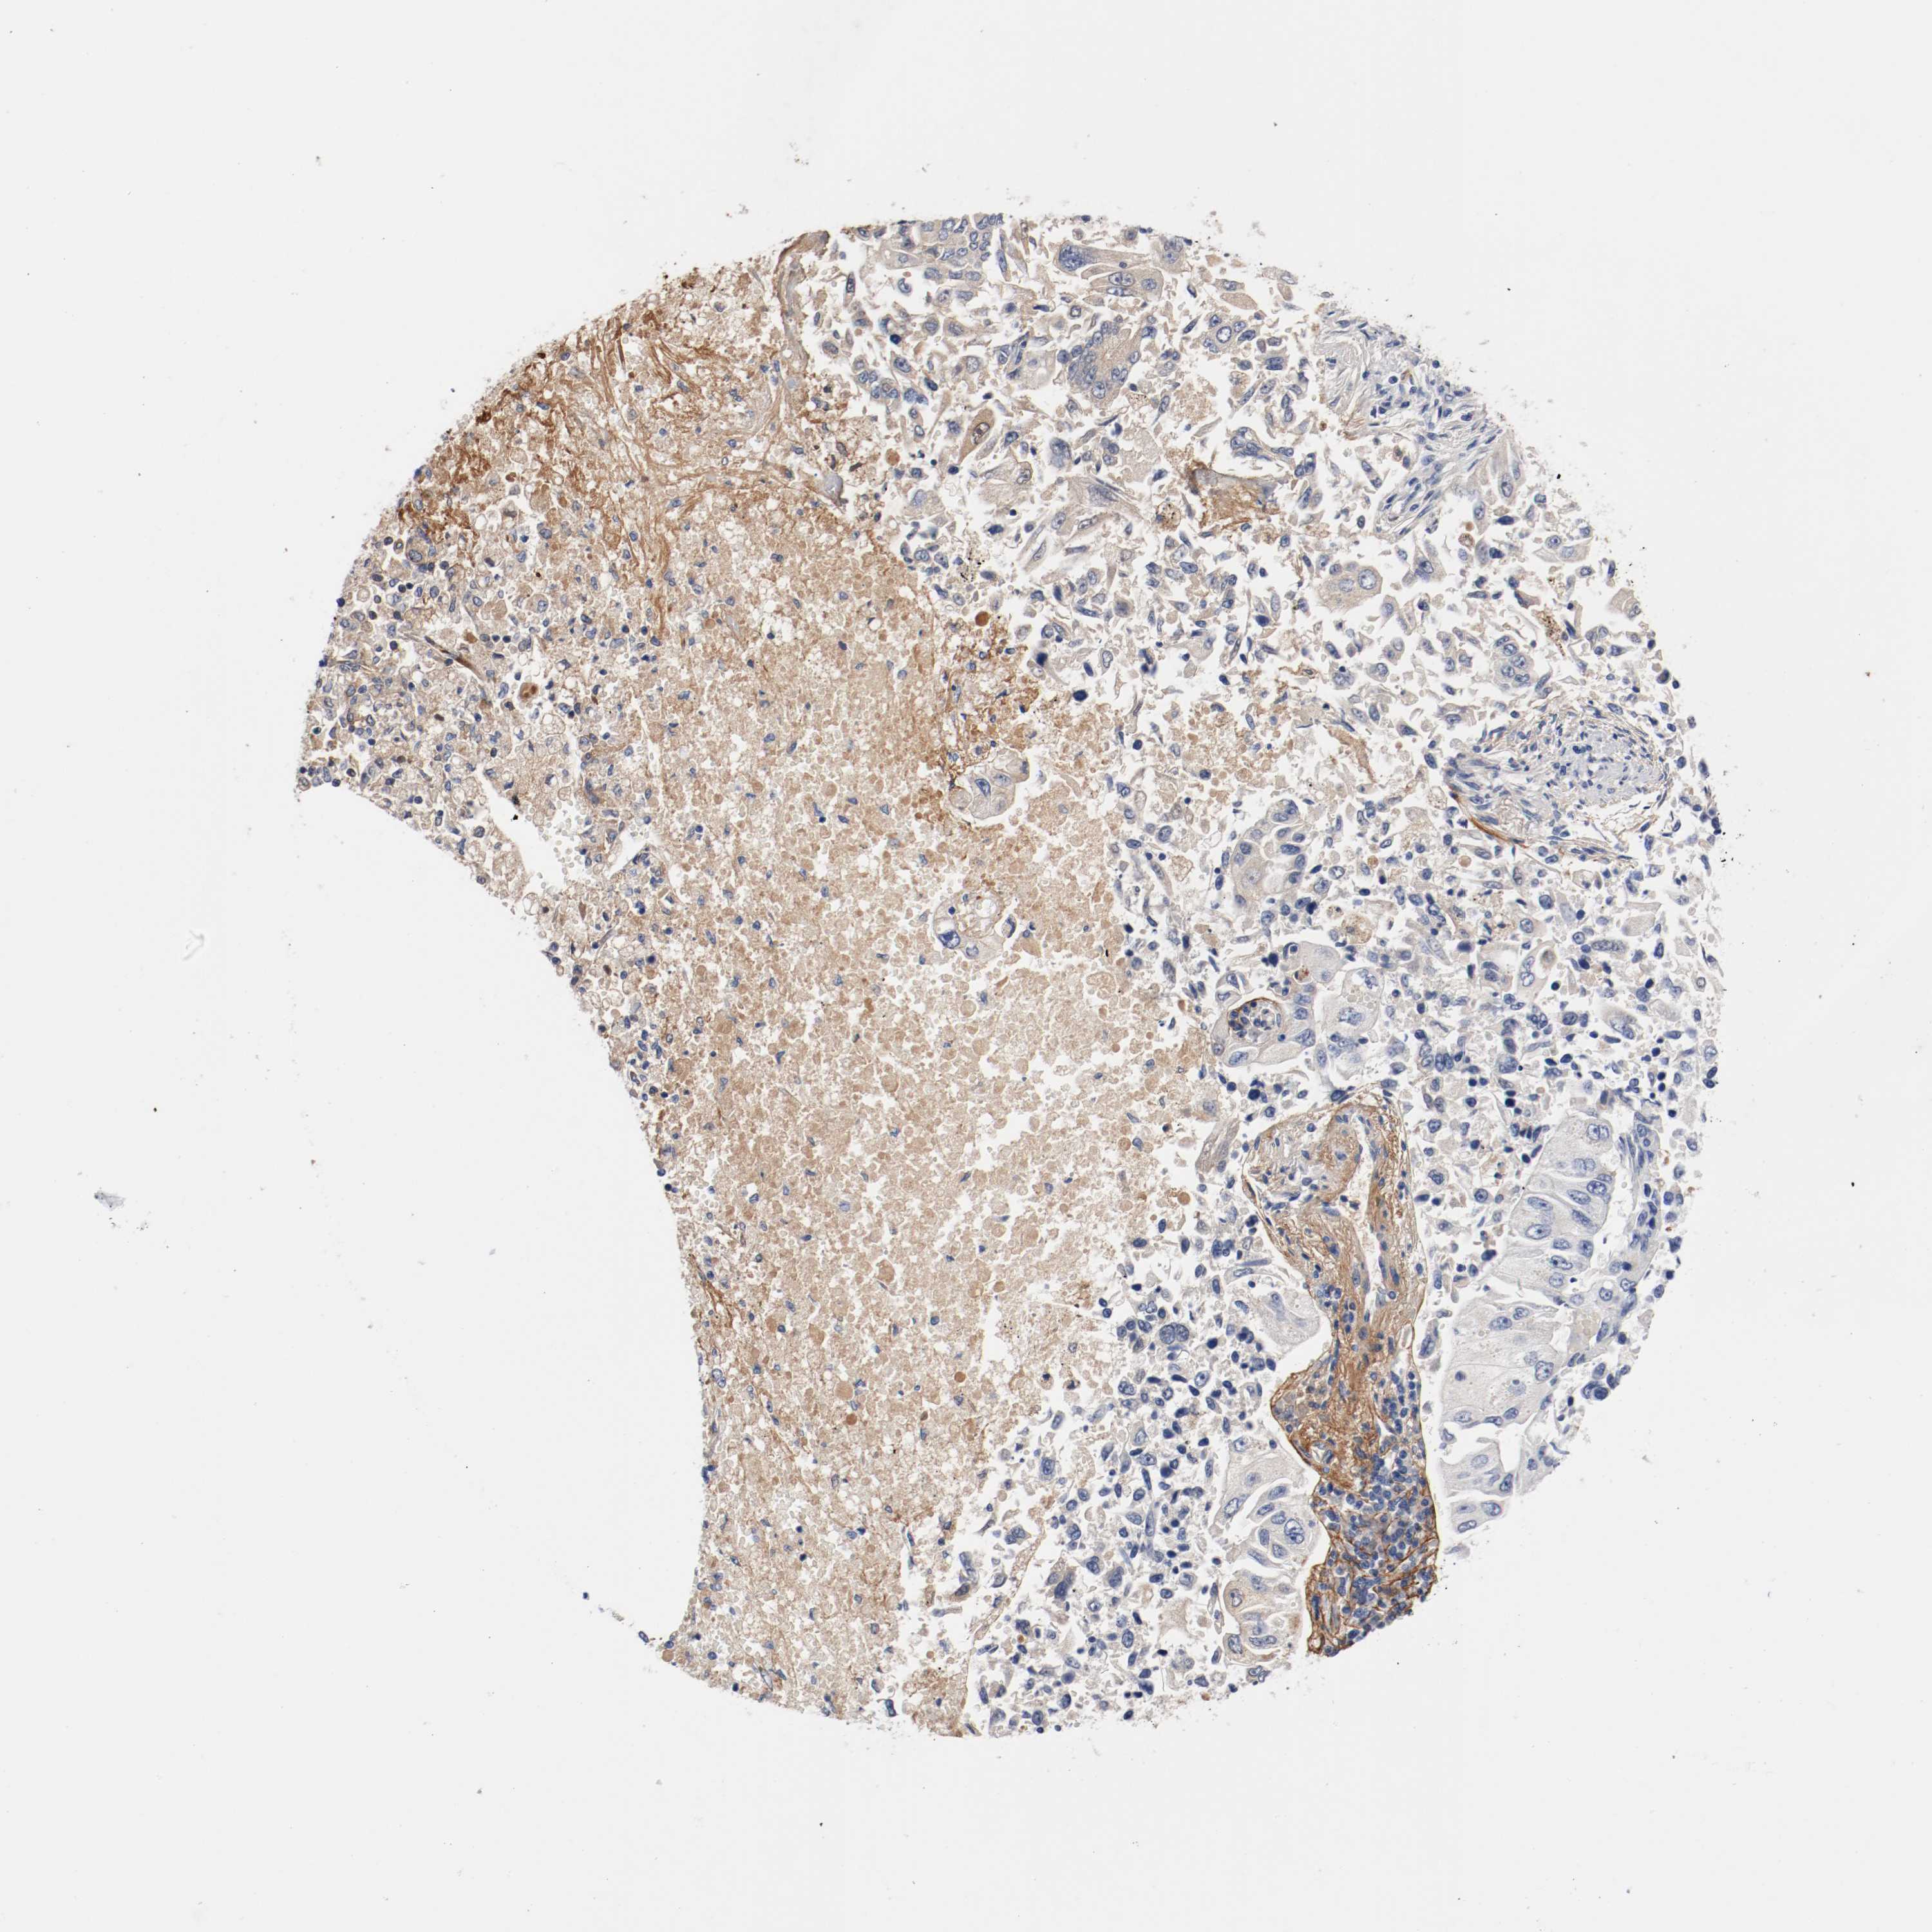

LUNG SQUAMOUS CELL CARCINOMA (TCGA) - Interactive survival scatter ploti

The Survival Scatter plot shows the clinical status (i.e. dead or alive) for all individuals in the patient cohort, based on the same data that underlies the corresponding Kaplan-Meier plots. Patients that are alive at last time for follow-up are shown in blue and patients who have died during the study are shown in red.

The x-axis shows the expression levels (FPKM) of the investigated gene in the tumor tissue at the time of diagnosis. The y-axis shows the follow-up time after diagnosis (years). Both axes are complimented with kernel density curves demonstrating the data density over the axes. The top density plot shows the expression levels (FPKM) distribution among dead (red) and alive patients (blue). The right density plot shows the data density of the survived years of dead patients with high and low expression levels respectively, stratified using the cutoff indicated by the vertical dashed line through the Survival Scatter plot. This cutoff is automatically defined based on the FPKM cutoff that minimizes the p-score. The cutoff can be changed by dragging the vertical line or by entering a cutoff value in the square labeled "Current cut-off".

Under the Survival Scatter plot the p-score landscape (black curve; left axis) is shown together with dead median separation (red curve; right axis). Dead median separation is the difference in median mRNA expression between patients who have died with high and low expression, respectively. It is calculated as follows: median FPKM expression of dead patients with high expression - median FPKM expression of dead patients with low expression. This is intended to aid the user in visually exploring custom cutoffs and the associated p-scores and dead median separation.

Individual patient data is displayed and can be filtered by clicking on one or more of the category buttons on the top of the page. Categories describing expression level and patient information include: high, low, alive, dead, female, male and tumor stages. The scale of the x-axis can be toggled between linear and log-scale by clicking on the "x log" button. Mouse-over function shows TCGA ID, patient information and mRNA expression (FPKM) for each patient.

& Survival analysisi

Kaplan-Meier plots summarize results from analysis of correlation between mRNA expression level and patient survival. Patients were divided based on level of expression into one of the two groups "low" (under cut off) or "high" (over cut off). X-axis shows time for survival (years) and y-axis shows the probability of survival, where 1.0 corresponds to 100 percent.

TNC is not prognostic in Lung Squamous Cell Carcinoma (TCGA)

Best expression cut offi

Based on the FPKM value of each gene, patients were classified into two groups and association between prognosis (survival) and gene expression (FPKM) was examined. The best expression cut-off refers the FPKM value that yields maximal difference with regard to survival between the two groups at the lowest log-rank P-value. Best expression cut-off was selected based on survival analysis .

When clicking on this number, the vertical dashed line indicating cut-off, the interactive survival plot, and the Kaplan-Meier curve will be adjusted to show results based on the best expression cut-off.

: 71.26

Average pTPM 146.2

Number of samples 489